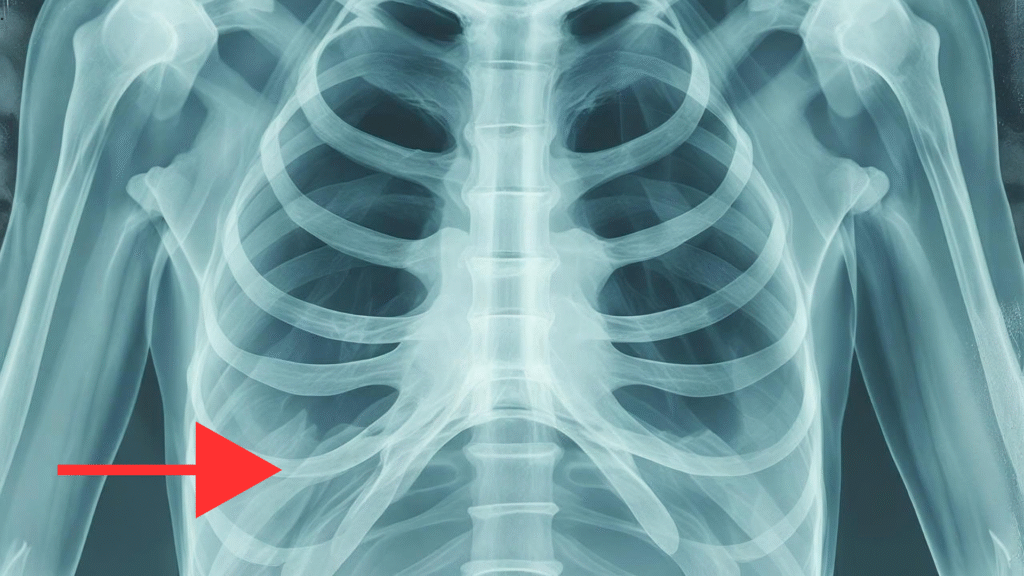

The temporomandibular joint (TMJ) is a vital component of jaw movement and overall facial function. When TMJ disorders involve severe joint damage, congenital deformities, or trauma, advanced surgical solutions such as a costochondral graft may be necessary. This procedure uses a small piece of the patient’s rib cartilage and bone to reconstruct the jaw joint, restoring function, aesthetics, and comfort.

- Harvesting the graft – A segment of the rib cartilage and bone is carefully removed.